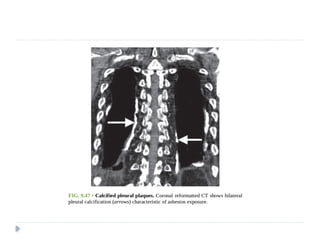

Pleural Plaques

 Pleural plaques are circumscribed collections of dense

collagenous connective tissue, which may or may not be

calcified,

 They represent the most common manifestation of and

serve as a biomarker of asbestos exposure

 The latency period between exposure to asbestos and

development of pleural plaques is approximately 15 years.

 The plaques involve mainly the posterior and

anterolateral aspects of the pleura, following the contours

of the posterolateral seventh to 10th ribs, and the domes

of the hemidiaphragms, and spare the lung apices and

costophrenic angles

 They almost always involve only the parietal

pleura but occasionally may be seen in the

visceral pleura in the interlobar fissures and

sometimes involve the pericardium

 On chest radiographs, pleural plaques are

unilateral in approximately 25% of cases

 more plaques are detected on CT than chest

radiography.